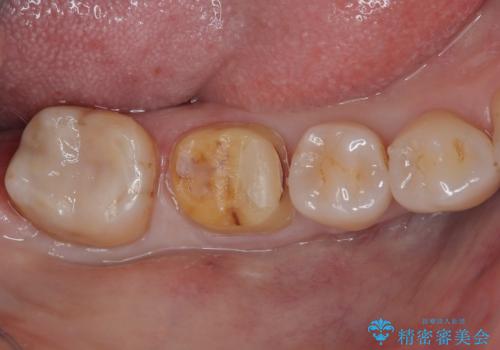

特に異常もなく見た目、噛み合わせともに満足していただけました。

ラバーダム防湿を行い、セラミックの接着をすることで、唾液や血液などの接着阻害因子を排除することができます。

歯と歯の間の虫歯をコンポジットレジンや保険のメタルインレーで治すと段差ができたりして清掃性が悪くなるので、セラミックインレー修復やゴールドインレー修復などの適合の良い詰め物で治療することをオススメします。又、適合の良い詰め物、被せものだと虫歯の再発リスクを低減できます。